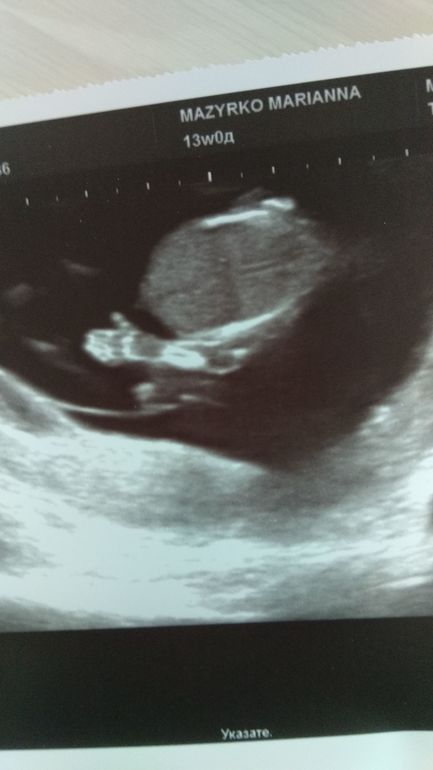

Так вот, ровно в 13 недель я сходила на скрининг эксперту по аномалиям плода Мазырко М.А., у нее есть аккаунт в Инстаграме, это что-то, столько фото и видео малышей). Конечно, это было прекрасно! Нам с мужем все показывали на экране, все рассказывали, все органы посмотрели, пальчики пересчитали, слушали сердечко, нам сказали пол - девочка, со словами "фирма гарантирует"😁. Малышка подтягивалась, трогала ручками личико, сосала пальчик. Я лежала и плакала от счастья, что все хорошо! А муж по дороге домой был под впечатлением, говорит, ну, только был размером с фасолинку, а там целый человечище, с ручками, ножками! Сам бы не увидел, не поверил). Дали фото и диск. Приехали домой, включили кино и позвали детей смотреть. Через пару минут они говорят, а чей это малыш? Я сказала - наш общий😊, дочь как стала плакать от счастья, обнимала меня, говорила, что так просила сестрёнку, и я с ней опять рыдала! Сын, через пару часов пришел и говорит, нужно купить посуды побольше, тарелки, чашки, ложки). На мой вопрос зачем, сказал, ну для малыша))). Я ему сказала, что малышу сися нужна будет первый год, а потом все купим).

Через 3 дня поехала на бесплатный скрининг от ЖК, на удивление, прождала всего 15 минут, на стене висел монитор, я все видела, но уже была абсолютно спокойна. Все посмотрела, правда на живот нажимала неприятно, даже предложила сказать пол, и, снова подтвердила девочку. Так же я попросила посмотреть шейку, т.к.пои выписке сказали короткая 30 мм, но смотрели по животу. Эта же врач посмотрела вагинально, и сказала, нормальная шейка 35.8 мм. И, подтвердила низкое расположение плаценты от зева, но, на таком сроке не ставят низкого предлежания, только на 2ом скрининге. Это расположение, видимо, и стало причиной кровотечения перед госпитализацией.